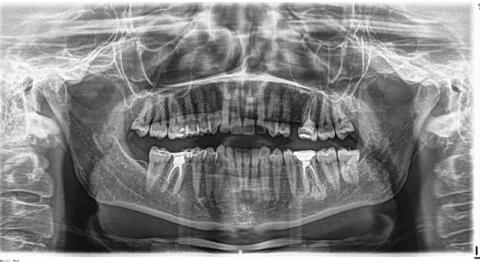

Також робиться знімок голови у боковій проекції (телерентгенограма). По рентгенівському знімку вираховуються математичні значення: кути, відстані між анатомічними утвореннями. По отриманим показникам вираховується норма і відхилення.